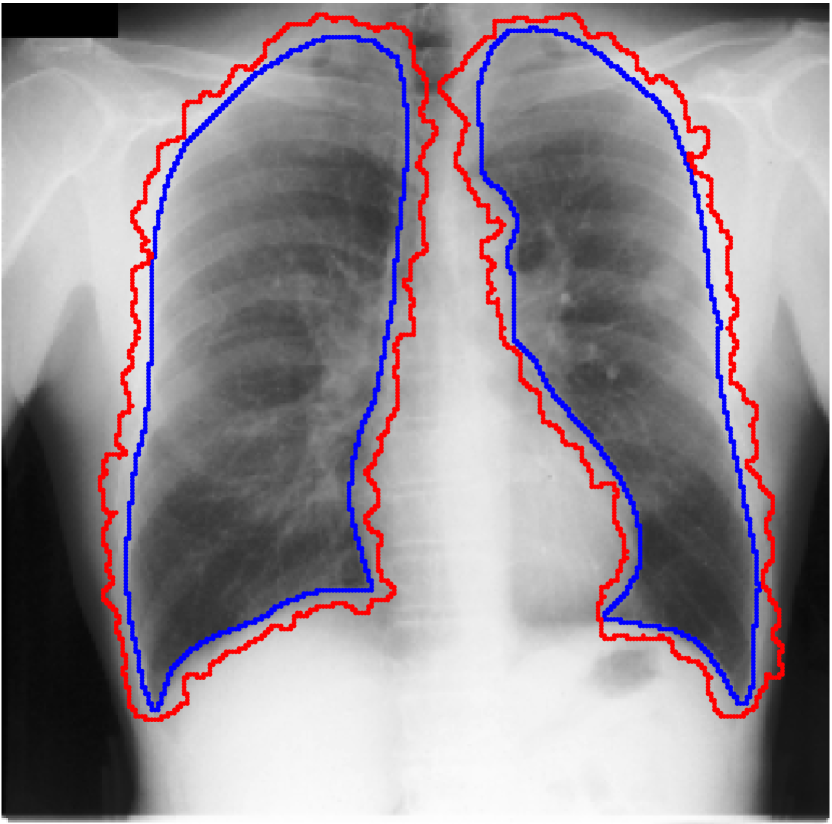

Table 1 shows the segmentation results of different methods with synthetic noisy label settings on JSRT , ISIC 2017 and Brats 2020 dataset. Note that QAM cannot be applied to Brats 2020 dataset because their network is designed for 2D only. We compare DICE score (DSC) on testing sets (against the clean labels). For each setting, we train 5 different models, and report the mean DSC and standard deviation. In and , where biases show up in noisy labels, the proposed method outperforms the baselines by a big leap in total case. The compared methods, however, only work when little bias is included, like . is equivalent to setting in our Markov model, resulting in . We also test the proposed method on real-world label noise, results shows in Table 2. Figure 5 shows examples of label correction results. We provide more qualitative results in the Appendix A.4.

Real-world label noise. To evaluate with real-world label noise is challenging. We are not aware of any public medical image segmentation dataset that has both true labels and noisy labels from human annotators. Therefore, we use a multi-annotator dataset, LIDC-IDRI dataset (Armato III et al., 2015; Armato et al., 2011; Clark et al., 2013), and the coarse segmentation in a vision dataset, Cityscapes (Cordts et al., 2016). The LIDC-IDRI dataset consists of 1018 3D thorax CT scans where four radiologists have annotated multiple lung nodules in each scan. The dataset was annotated by 12 radiologists, and it is not possible to match an annotation to an expert. We use the majority voting as the true labels and the union of four annotations as noisy labels. We process and split the data exactly the same way as Kohl et al. (2018). Cityscapes dataset contains 5000 finely annotated images along with a coarse segmentation by human annotators that we use as the “noisy label”. We only focus on the ‘car’ class because (1) cars are popular objects and are frequently included in images; (2) the coarse annotation of cars is very similar to noisy annotation in medical imaging – they are reasonable distortions of the clean label without changing the topology. See Figure 4(c) for an example. The detailed settings of LIDC-IDRI and Cityscapes can be found in Appendix A.2.1.